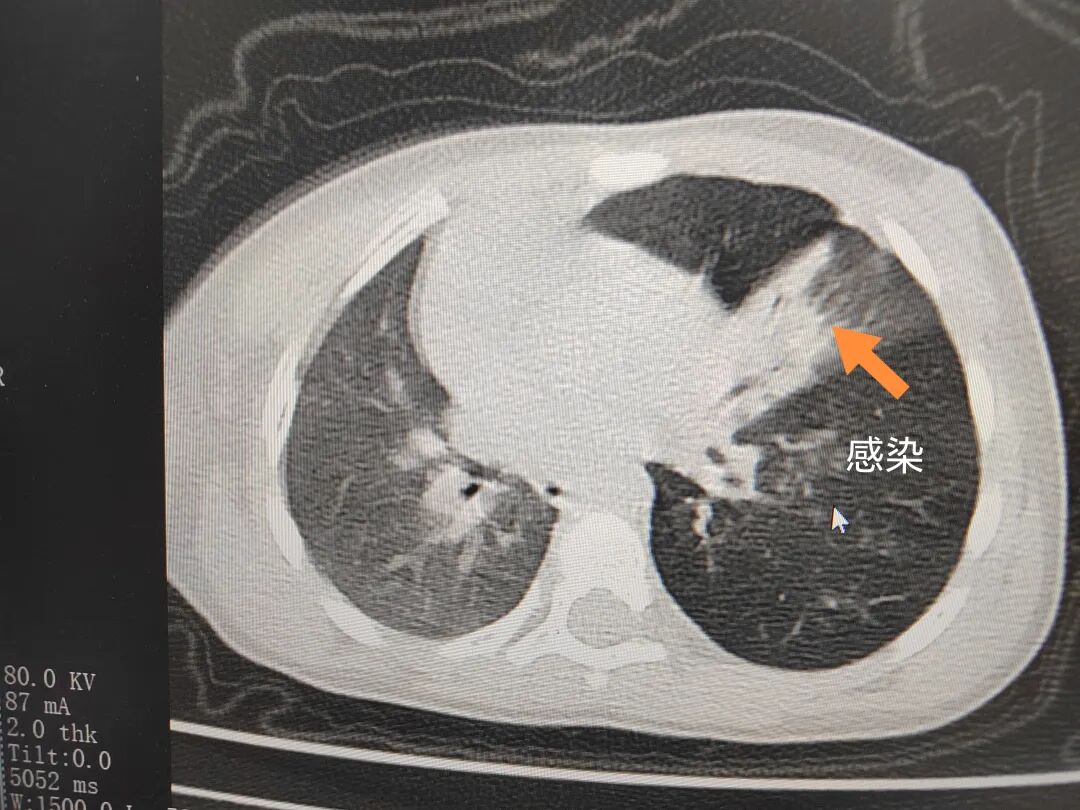

三天后(11月13日),趙寶出現(xiàn)高熱、咳喘加重,家長著急了,再次帶他來到醫(yī)院。CT檢查顯示左肺過度充氣,左肺上下葉支氣管主干見不規(guī)則高密度影,左肺上葉可見大片狀密度增高影,縱隔窗實變,提示為“左側(cè)支氣管內(nèi)異物并繼發(fā)性改變,左肺上葉舌段肺膨脹不全”。